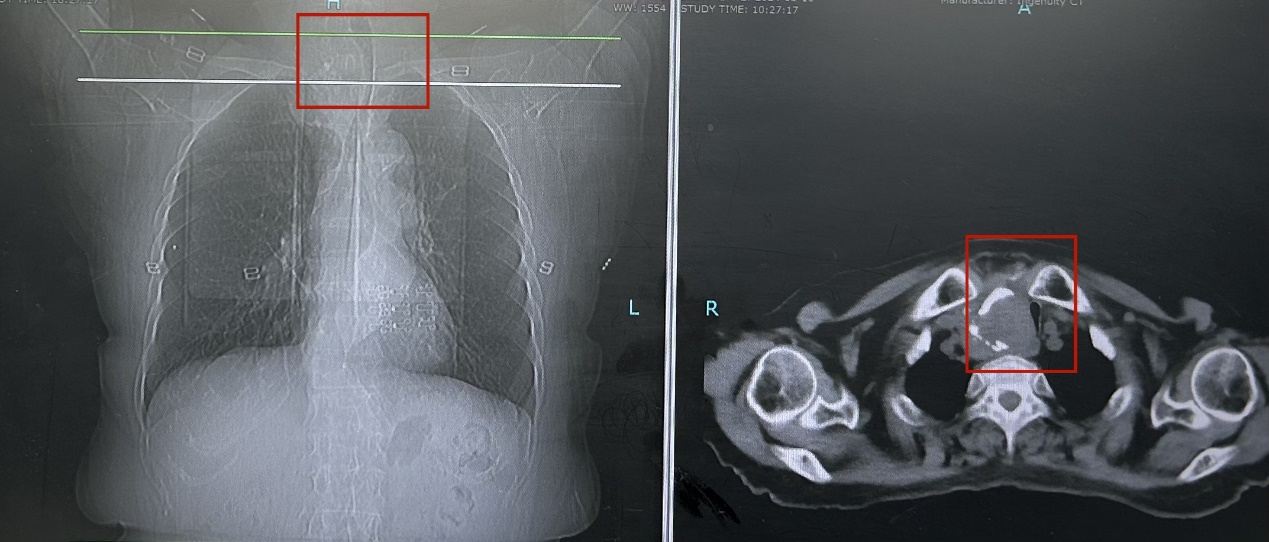

意识到问题严重性的她来到北京中医医院普外/肿瘤外科甲状腺专病门诊就诊。经过检查发现,齐阿姨的甲状腺肿物已经长到接近15厘米大小,坠入到胸骨后,气管已经被巨大的甲状腺肿物压迫的歪向左侧,最狭窄处仅剩3.9毫米。如果肿物继续增长,齐阿姨就面临着无法呼吸的风险,手术治疗迫在眉睫。

气道受压变形

气管受压严重、受压区域长,位于胸骨后、距离气管隆突近的“一线天”气道,是名副其实的“困难气道”。考虑到齐阿姨气道情况特殊,不仅气管插管风险较大,也存在术后气管塌陷的可能,普外/肿瘤外科主任路夷平组织详细的术前讨论,并组织召开多学科疑难病例讨论,麻醉科、放射科、重症医学科、护理团队、医务处参加。为保障患者手术顺利进行,麻醉科主任丁玲玲多次进行会诊。放射科副主任霍健伟、重症医学科副主任医师王旭升详细分析患者影像资料,认为肿物良性可能性大,通过分析病变压迫气管形态,考虑肿物硬度偏软,气管插管有通过气管狭窄段的机会。